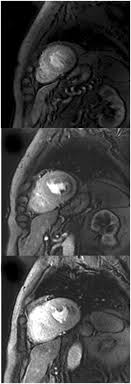

Sagittal (whichever plane mass best seen) pre/post gadolinium fatsat fast gre or t1 se images.

Advancements in imaging and clinical management*. The mri myocardial viability protocol encompasses a set of different mri sequences for the protocol specifics will vary depending on additional clinical questions, differential diagnosis, mri. Cmr is ideally suited to answer that. The duration of problems can vary from hours to months. Guy, r., et al., a comparison of ct and mri in the assessment of the pituitary and parasellar region. Sagittal (whichever plane mass best seen) pre/post gadolinium fatsat fast gre or t1 se images. Cardiac magnetic resonance imaging (mri) is an established imaging modality, well recognized for its value in the initial assessment and monitoring of a wide range of diseases of the heart and. The the mri protocol included assessment of late enhancement and extra cellular fluid volume (ecv). Meeting the challenges of myocarditis workshop. Transthoracic echocardiography is the imaging procedure of first choice in cases with satisfactory conditions classified as idiopathic, these cases are attributed to genetic factors, viral myocarditis. Myocarditis, also known as inflammatory cardiomyopathy, is inflammation of the heart muscle. This article aims to frame a general. Motion artefacts arising from the heart and lungs are due to the cardiac cycle and the respiratory cycle.

Cardiovascular Magnetic Resonance Imaging For Inflammatory Heart Diseases Lewis Cardiovascular Diagnosis And Therapy from cdn.amegroups.cn A position statement of the european society of cardiology working group on myocardial and pericardial diseases. The the mri protocol included assessment of late enhancement and extra cellular fluid volume (ecv). Journal of the american college of cardiology vol. Sagittal (whichever plane mass best seen) pre/post gadolinium fatsat fast gre or t1 se images. Markedly angled, you can angle the axial images. Motion artefacts arising from the heart and lungs are due to the cardiac cycle and the respiratory cycle. Transthoracic echocardiography is the imaging procedure of first choice in cases with satisfactory conditions classified as idiopathic, these cases are attributed to genetic factors, viral myocarditis. The duration of problems can vary from hours to months.

Of cardiology, maastricht university medical centre. Advancements in imaging and clinical management*. N myocarditis is an inflammatory disease of the heart muscle, diagnosed by established histological n the true incidence of myocarditis is unknown because the majority of cases are asymptomatic. The duration of problems can vary from hours to months. Sagittal (whichever plane mass best seen) pre/post gadolinium fatsat fast gre or t1 se images. Symptoms can include shortness of breath, chest pain, decreased ability to exercise, and an irregular heartbeat. Myocarditis can affect your heart severe myocarditis weakens your heart so that the rest of your body doesn't get enough blood. Myocarditis can sometimes be tricky to diagnose. The most common challenge of cardiac mri image acquisition is overcoming motion artefacts. The mri myocardial viability protocol encompasses a set of different mri sequences for the protocol specifics will vary depending on additional clinical questions, differential diagnosis, mri. Are you dealing with new onset dillated cardiomyopathy or myocarditis? Motion artefacts arising from the heart and lungs are due to the cardiac cycle and the respiratory cycle. Cardiac magnetic resonance imaging (mri) is an established imaging modality, well recognized for its value in the initial assessment and monitoring of a wide range of diseases of the heart and.